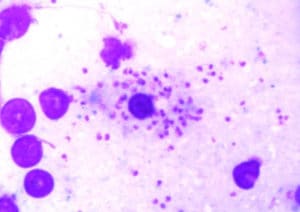

Костный мозг собаки, больной лейшманиозом

Многочисленные амастиготы с круглым ядром и плоским кинетопластом присутствуют в цитоплазме макрофага (окраска по Райт-Лейшману).